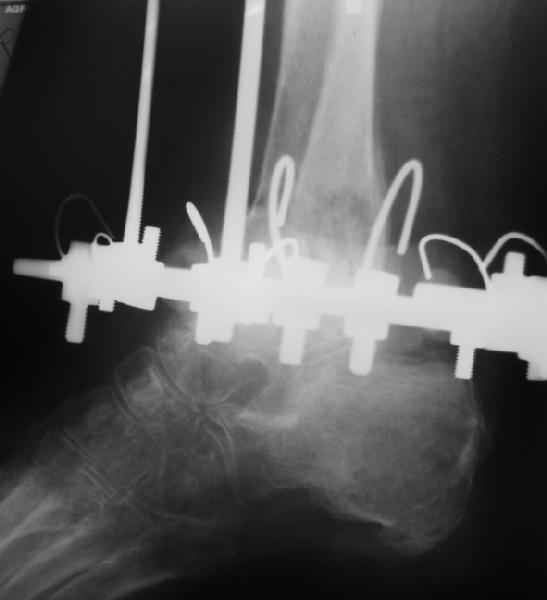

Пациентка 56лет поступила через 5,5 мес. после открытого 2-х лодыжечного перелома, наружного вывиха правой стопы, осложнённого гнойным артритом.

через 3 недели после травмы в ОКБ выполнена артротомия, некрсеквестрэктомия б/берцовой кости, ещё через неделю - аутодермопластика по Тиршу. К нам больная поступила через 5,5 мес. Выполнен ЧКО, остеотомия м/берцовой кости, аппаратное вправление вывиха. Планируется артродез голеностопного сустава. По медиальной поверхности голени на месте аутодермопластики сформировался грубый рубец, спаянный с б/берцовой костью. Больная ходит на костылях с частичной опорой на правую стопу. ВОПРОС: 1) возможно ли в данной ситуации обойтись компрессионным артродезом в АВФ?2) какой вид кожной пластики и в какие сроки целесообразен?

Возможно, но тогда дополнить аппарат модулями на стопе. На фото стопа в эквинусе. Сомнительно, что фиксация только за таран удержит всю стопу, тем более при разрешенной нагрузке.

"На фото стопа в эквинусе."

Обратите внимание на установку тарана на рентгене!

В самом деле, снимки некачественные - таран в ротации. Но даже по ним видно, что установка стопы минимум 104 градуса. С одной стороны - В Илизаровской технике пишут, что для женщин допустимо и 110. С другой - почему-то в цивилизованном мире настаивают на четких 90.

А если еще лучше присмотреться, таран в переднем подвывихе, что не кажется допустимым.